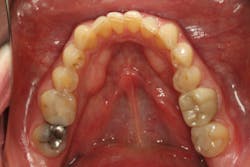

From the two-dimensional evaluation, the signs of occlusal instability were clear. Darren had very thin, chipping incisal edges, to the point where they were becoming transparent. The patient had almost worn shelves into the lingual of the maxillary anteriors, suggesting a restricted envelope of function. He also had wear into dentin in the anterior teeth as well as posterior teeth, and his anterior teeth had Class 1 mobility.

Luckily, the patient was a Piper TMJ Classification 1 with healthy intact joint assembly. His functional problems were primarily occlusal-muscle. But the dentition also exhibited signs of acid corrosion in a presentation that suggested gastroesophageal reflux disease (GERD), so we referred Darren to his physician where he was treated for GERD prior to starting any dental treatment.

Orthodontics also allowed us to be more conservative in our tooth preparation. We wanted to minimize the amount of tooth structure that we had to reduce on the lingual of the maxillary incisors, since we were already missing a good amount of tooth structure from wear. Orthodontics also allowed the possibility to avoid any preparation or indirect restorations on the mandibular anterior teeth that otherwise would have been required to work out the anterior guidance. Darren was aware that we would need to make that final determination once the orthodontics treatment was completed.